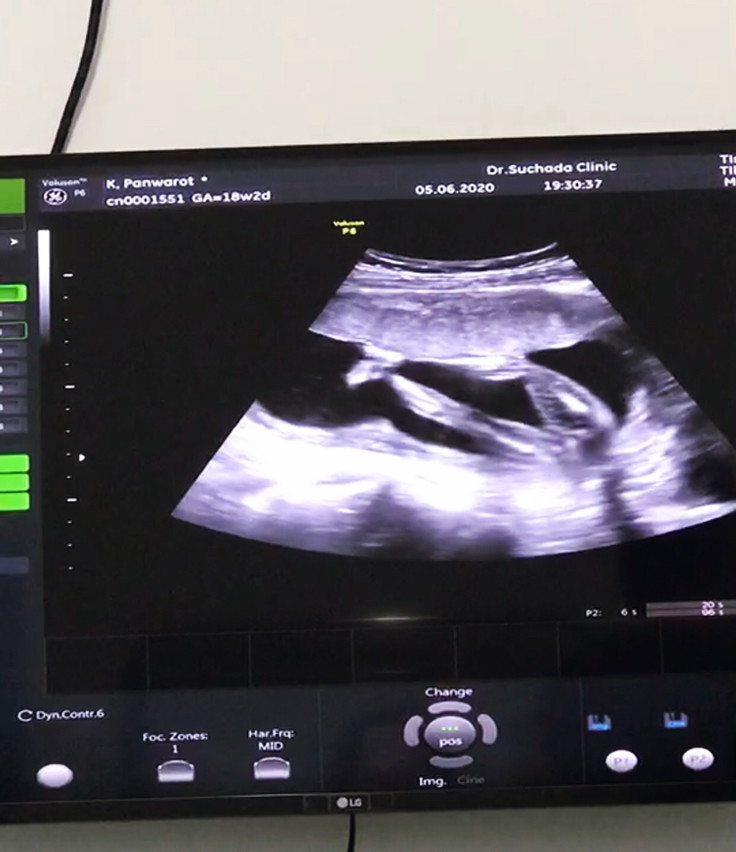

ขอดู รูปซาว หน่อยค่ะว่าเหมื่อนกันไหม หมอ บอกว่า เป็น ญ เพราะไม่มีจู๋โผลมา บ้านอื่น ได้ ญ แบบนี้หรือเปล่าค่ะ แม่แอบกังวล อยากได้ญ กลัว จู่ โผล่มาทีหลัง 😁23+4.

บ้านนี้คุณหมอว่าเป็นผู้หญิงตั้งแต่24สัปดาห์